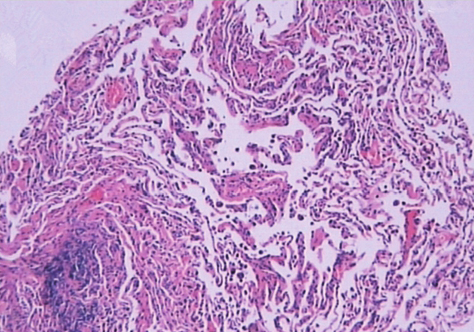

1小时条评论51岁男性,因咳嗽8个月,胸闷伴气促1个月入院。如何诊治? 一、入院疑诊 (一)病例信息 【病史】 男性患者,51岁,因咳嗽8个月,胸闷伴气促1个月入院。患者于8个月前,感冒后开始出现咳嗽,偶有咳痰,痰为黑色、量少,无畏寒、发热、胸痛、胸闷、咯...